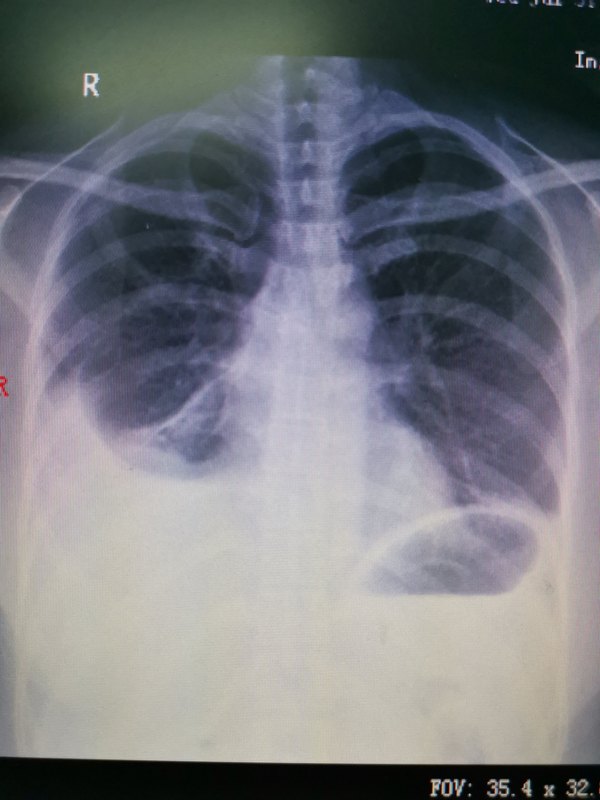

看肺小結節(jié)門診,有不少外院醫(yī)生推薦來的病人,也有不少在患者群中打聽后來的病人。有個病人說:聽說你對肺小結節(jié)是保守治療派的我告訴他:我不是支持肺結節(jié)都保守治療,而是希望去接受手術的病人都是真正需要手術的病人!即“疑病從緩”!疑病從緩會讓結節(jié)發(fā)展到肺癌晩期嗎?可以負責任地說,遵醫(yī)囑適當時間的隨訪觀察并不會錯過結節(jié)手術的最佳時間,并不會因觀察就發(fā)展到晚期!所以大可放心。當然,真正我判斷惡性可能大的病人我一定會堅持推薦其做手術的!近年來,我們推薦去手術的亞厘米結節(jié)沒有一個誤手術的! 為什么不要隨便去做手術呢?因為1.有的病人因良性結節(jié)誤手術,白挨一刀,身體心理都受到很大的創(chuàng)傷;2.手術后有不少病人出現(xiàn)胸痛、咳嗽甚至胸腔積液(圖1),肺功能下降;3.有的病人小結節(jié)(圖2)手術后一段時間,余肺再次出現(xiàn)磨玻璃小結節(jié)(圖3),處理就非常棘手! 總之,對太小、太深、太淡、太純、太多、太老(年齡)、太差(肺功能)的肺小結節(jié),我都是保守的,如果推薦手術治療,那就是有理由考慮惡性風險大且有微浸潤變化的趨勢!

71歲老年女性,查體發(fā)現(xiàn)左肺磨玻璃結節(jié)約1.2CM,周圍毛刺,似有血管進入(圖一)!經(jīng)某肺結節(jié)專家工作室專家考慮肺癌,已住院擬做手術!家屬帶片來我門診就診,我建議抗炎治療后3個月復查!患者出院后近日復查CT示肺部磨玻璃影已完全消失(圖二)!一家人非常高興,老太婆一定要親自來面謝![偷笑]有時啊,不要太著急,讓子彈飛一會兒,對肺小結節(jié)是個非常不錯的選擇!